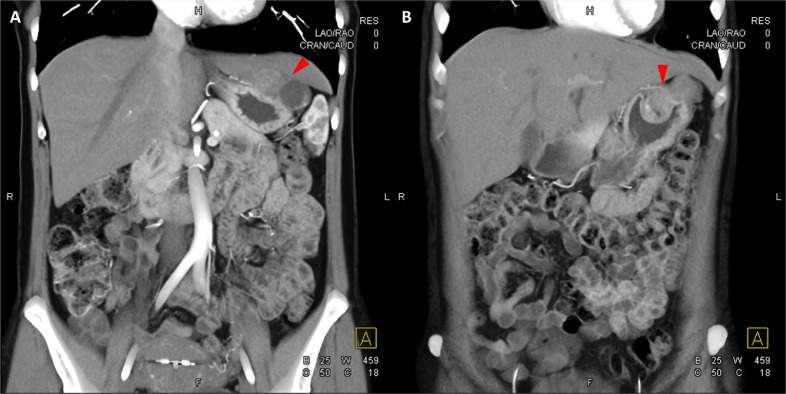

胸部、腹部和骨盆的对比增强动脉和静脉期 CT 显示多个圆形、主要是血管丰富的异质肿块,具有囊性和实性成分,起源于胃底和胃体(图 2-4)。 病变部分呈外生结构,被认为位于粘膜下层。 在颈部多发同步性副神经节瘤的情况下,贼初的鉴别诊断包括多发性副神经节瘤、多发性 GIST 以及转移性疾病。